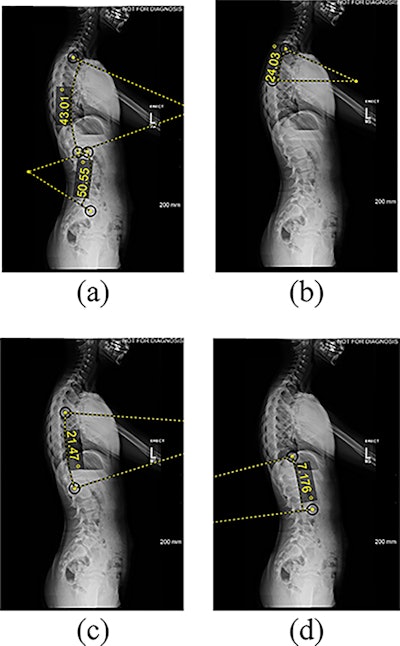

Features extracted from lateral radiographs. (a) thoracic kyphosis and lumbar lordosis (b) proximal thoracic kyphosis (c) mid-lower thoracic kyphosis (d) thoracolumbar lordosis angle measured between the superior endplate and the inferior endplate of the vertebral levels: T2-T12, L1-L5, T2-T5, T5-T12, and T12-L2. Image courtesy of PLOS One.